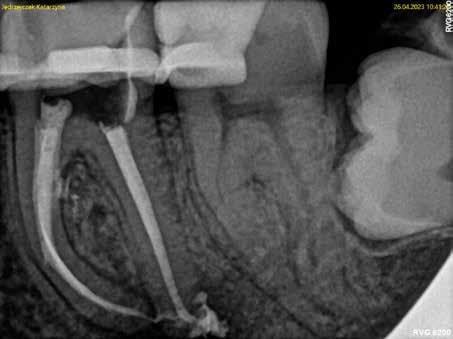

A páciens a jobb alsó első nagyőrlőfogából kiinduló közepes erősségű fájdalom miatt kereste fel a rendelőnket. Periapikális röntgen és CBCT-felvétel is készült. Mindkét felvétel a mesiobukkális gyökércsúcs körül található radiolucens elváltozás jelenlétét igazolta. Ezenfelül a mesialis gyökérben két betört eszközdarab is észlelhető volt. Az egyik a középső gyökéri harmadban a gyökérgörbület előtt volt megtalálható, a másik pedig kicsivel a gyökérgörbület után (12–13. ábra).

A terület érzéstelenítését és kofferdám felhelyezését követően a meglévő kompozittömést eltávolítottuk és a gyökértömés elkészítéséhez szükséges körülmények biztosításához folyékony kompozit és folyékony kofferdám felhasználásával egy ideiglenes felépítményt készítettünk (14–17. ábra). Ezt követően eltávolítottuk a gyökértömő anyagot a mesialis és a disztális gyökércsatornákból. A betört eszközökhöz való hozzáférés biztosítását követően a magasabban elhelyezkedő fragmentumot egy ultrahangos eszköz segítségével eltávolítottuk (18. ábra). Ezután a mélyebben fekvő darab koronális vége is láthatóvá vált. Sajnos az eltávolítandó gyökérkezelő tű a közepén kettétört és csak a koronálisabban fekvő részét sikerült eltávolítani (19. ábra). Mivel az apikális fragmentumra nem láttunk rá közvetlenül és az átöblítés, valamint aktiválás hatására sem emelkedett ki a csatornából, ezért az eszköz mellett történő elhaladás megkísérlése mellett döntöttünk. A CBCT-felvétel tanulmányozása során nem tudtuk egyértelműen megállapítani, hogy a két mesialis csatornának vajon egy közös vagy két különálló kivezetőnyílása van, ezért a mesiolingualis csatorna megmunkálása közben periapikális röntgenfelvételt készítettünk. A röntgenfelvétel alapján vagy egy lépcső-

képződés alakult ki a csatornán belül, vagy a mesialis gyökér két különálló kivezetőnyílással rendelkezik (20. ábra). A gyökércsatorna átöblítése során 300/20 SWEEPS vezetőszálat

12. ábra: A kiindulási CBCT-felvételen jól látható a periapikális felritkulás. – 13. ábra: A kiindulási röntgenfelvételen látható a két betört eszközdarab.